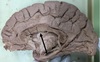

1. Identify 2 2. Identify 3 3. Identify 4 4. Identify 5 5. Identify 6

1. Falx Cerebri 2. Corpus callosum 3. Midbrain 4. cerebellum, grey matter 5. basilar artery

1. Name the dural venous sinuses related to number 2 2. Name the parts of number 3 3. Name the grey matter mass present in the white matter of structure 5

1. Superior and inferior saggital, straight sinus. 2. Rostrum, genu, trunk/body and spleenium 3. cerebellar nuclei